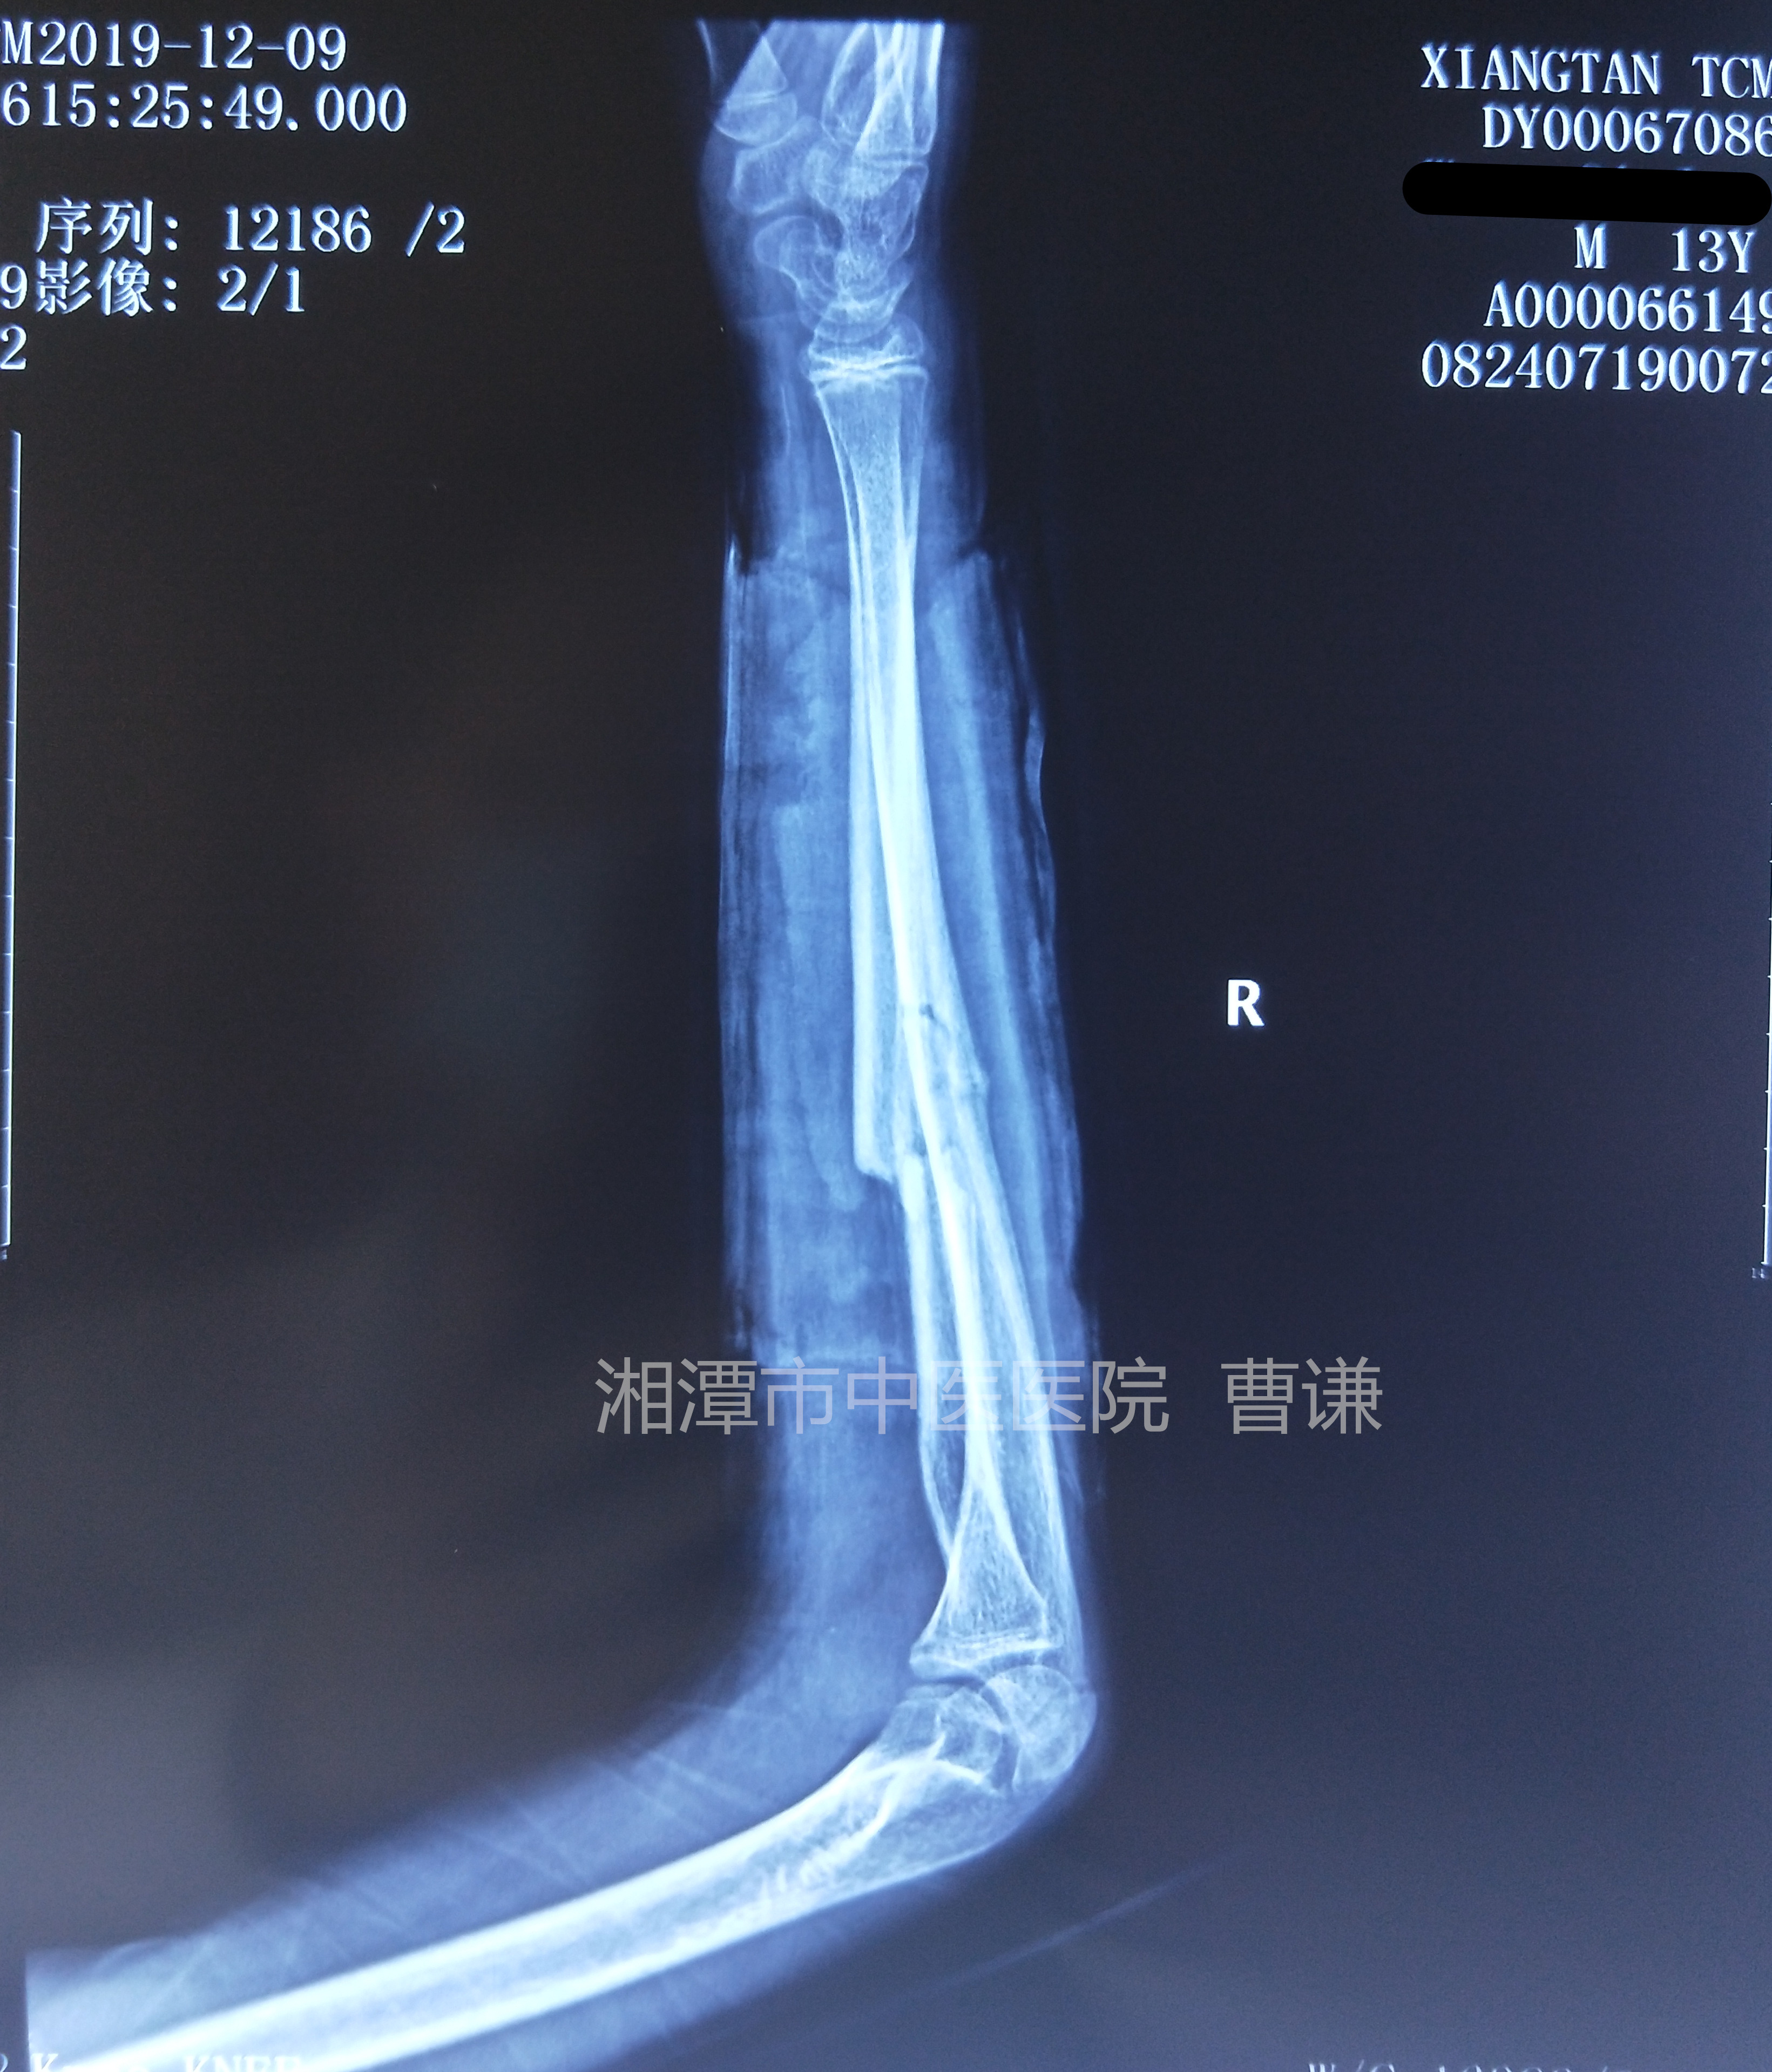

简要病史:跌倒致右前臂畸形、肿痛、活动受限,就诊于我院,拍片诊断为尺桡骨折中段骨折,建议手术治疗,患者要求保守治疗

临床诊断:右尺桡骨中段骨折

入院拍片情况如下: